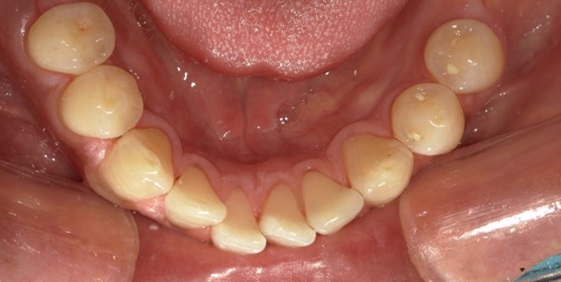

クリーニングは、取り切ることができないプラークや、プラークが固まってできた歯石を、スケーラーなどの歯科医院専用の機器を使って、しっかり落とすためのものです。

プラークや歯石は、むし歯や歯周病の原因菌の棲み家となり、口臭の原因にもなりますので、定期的にクリーニングを行うことが予防につながります。

歯のクリーニングをすることで、歯垢や汚れはもちろん、毎日の歯磨きでは落としきれない歯石が落とせます。

歯周病・虫歯・口臭などを引き起こす厄介な歯石を除去することで、口の中が健康的な状態に保ちやすくなることも大きなメリットと言えるでしょう。